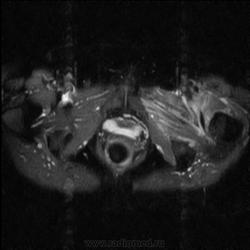

МРТ тазобедренный сустав (срочно)

Пациентка 1944г. р. Жалобы на боль области сустава в течении месяца. Температуры не отмечала. Серьезных травм со слов не было. Внешний осмотр новых данных не дал.

Дайкомы пока не смотрела-скорость интернета дома небольшая.Думаю, что здесь проблемы в суставе и параартикулярных мягких тканях.Не так давно у меня что-то похожее было.

типа бурсита тазобедренного сустава? подвздошно-гребешковая сумка получается

А как вам стенка прямой кишки?

Да, еще подвздошная область.

Подозрительная, но неубедительно пока.Ни одного сагитталла не вижу с прямой кишкой.Нужно дообследовать однозначно.

Ну сагитталы на сустав делали..придет за ответом дообследую и кишку, хотя она вполне доступна и для ректороманоскопии.